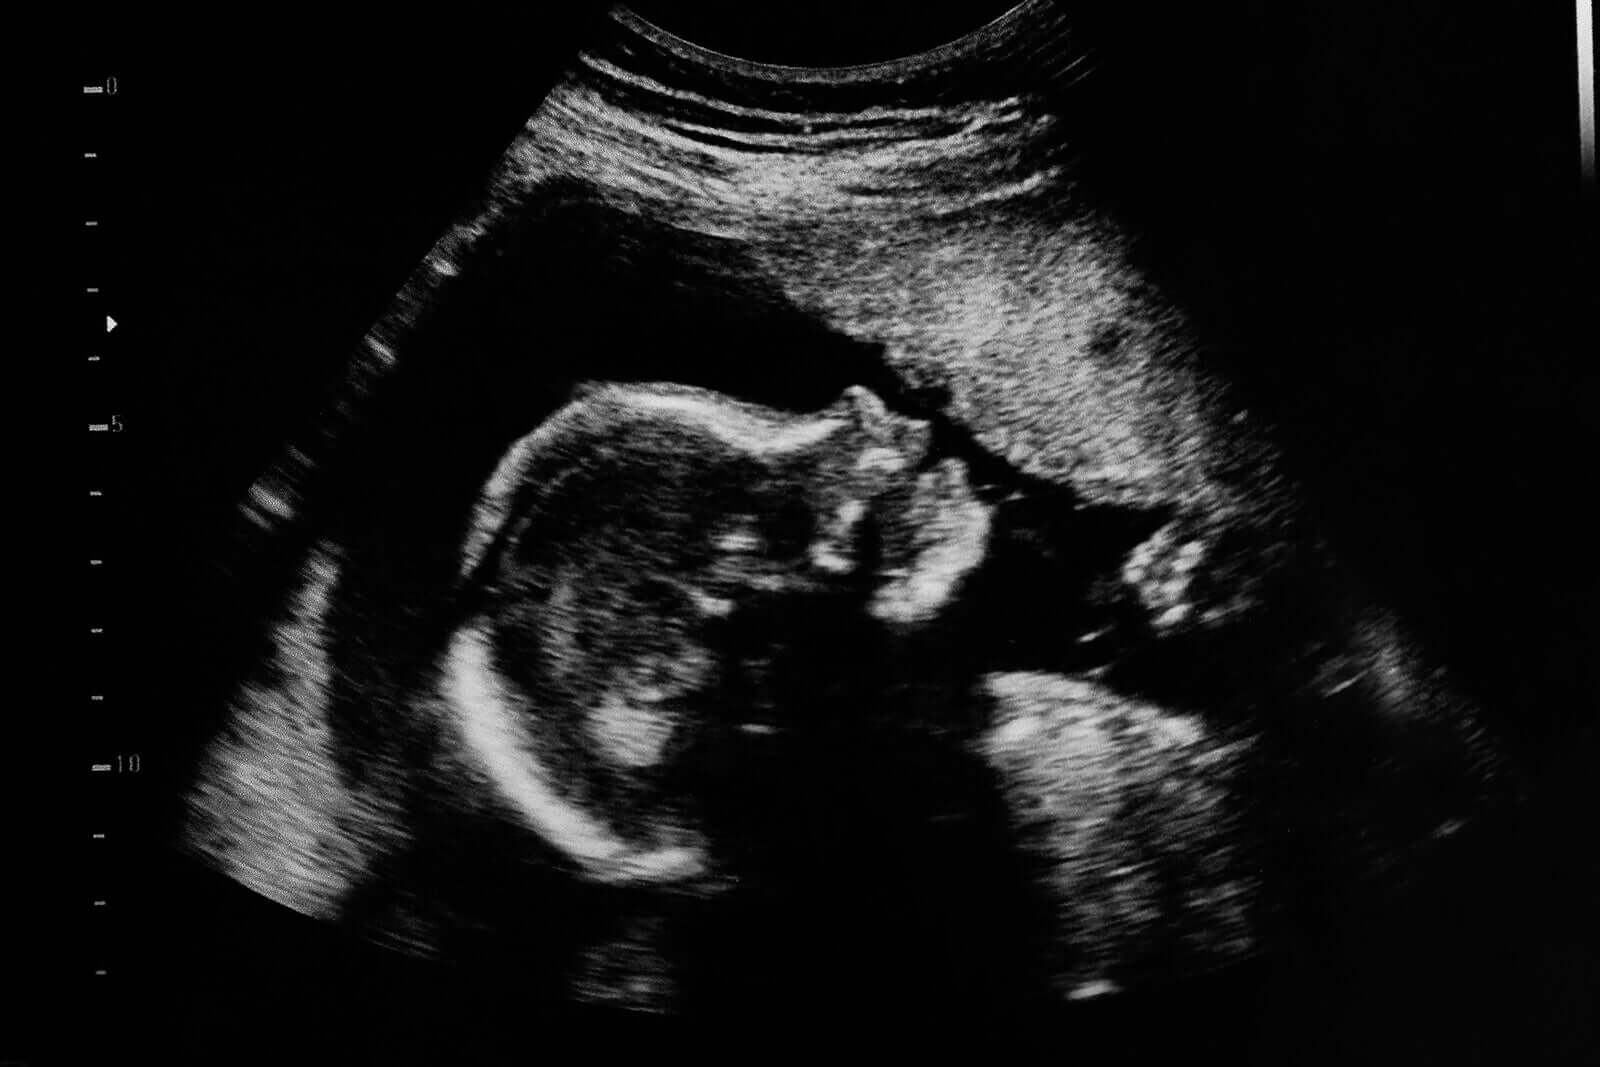

En morfologisk ultraljud är en icke-invasiv studie som försöker utvärdera hur barnets kropp utvecklas inuti moderns livmoder. Genom detta är det möjligt att upptäcka specifika fosterpatologier, så som medfödda missbildningar. under ett tidigt stadium.

Det innebär användningen av en maskin som avger högfrekventa ljudvågor genom kvinnans buk.

Ljudet sprids genom fostervattnet och “krockar” med barnets olika strukturer. Detta genererar en svarssignal (ett eko), som en dator fångar upp och visar som en 2- eller 3-dimensionell bild av barnet.

Ultraljud tjänar många syften under hela graviditeten. Huvudsyftet med andra trimesterns ultraljud är dock att utvärdera hur barnets olika organ har blir bildade.